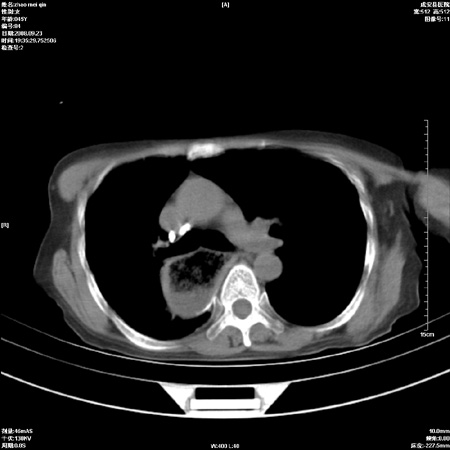

标题: CT15861:女 60 外伤后1小时 胸疼 [打印本页]

标题: CT15861:女 60 外伤后1小时 胸疼

外伤后1小时 胸疼 是外伤后引起的吗?

食道扩张明显下端逐渐变窄,倒像贲门失迟缓

食道ca术后胸腔胃,右肺挫伤?

非外伤性改变,典型的贲门失迟缓症

食道扩张明显下端逐渐变窄,大量食物存留,象贲门失迟缓症。